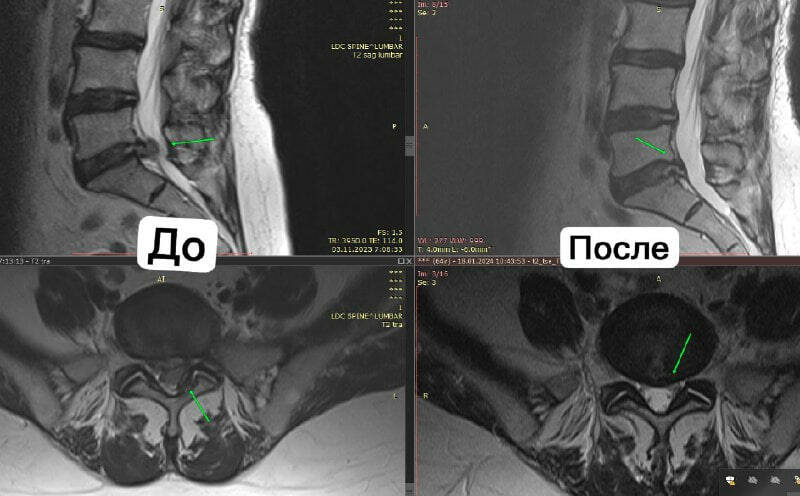

Кагыйдә буларак, дәвалау 10-12 катнаш сеанстан башлана. Идеалда клиникага көн саен йөрергә кирәк, тик без барысын да аңлыйбыз: кемгәдер – офиска барасы, кемнеңдер командировкага китәсе була. Шуңа күрә әгәр көн саен йөреп булмаса, курска төзәтмәләр кертелә ала. Берсендә процедуралар күбрәк булырга мөмкин, кайсындадыр сеансларны арттырабыз. Гадәттә, сеанс 1-1,5 сәгать була. Стимуляция этабы төгәлләнгәч, без пациентка гадәттә 2-3 айга каникул бирәбез. Шуннан соң ул контроль МРТ ясый. Шулай итеп без дәвалану нәтиҗәсен бәялибез һәм өйрәнәбез һәм резорбция стимуляциясен дәвам итәргәме әллә инде ахыргы нәтиҗәгә ирешелгәнме икәнен хәл итәбез. Менә карагыз, мәсәлән: бу МРТ арасында 2 ай аерма, пациентка 66 яшь, хәтта шушы кыска вакыт эчендә дә өлкән яшьтә искиткеч нәтиҗәләргә ирешеп була.

Тагын бер мисал: пациентка 25 яшь, МРТлар арасында – 6 ай. Бүсер 2 курстан соң юкка чыкты.